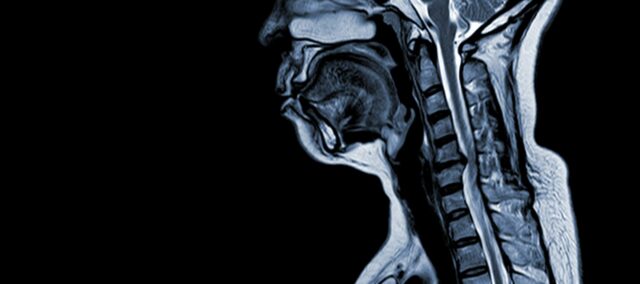

Die zervikale spondylotische Myelopathie (CSM) ist eine neurologische Erkrankung, die die häufigste Ursache für Rückenmarksverletzungen bei Erwachsenen darstellt. Vereinfacht ausgedrückt handelt es sich um eine Kompression oder Schädigung des Rückenmarks im Nackenbereich, die in erster Linie auf den natürlichen Alterungsprozess zurückzuführen ist, der die Halswirbel betrifft. Der Begriff "Myelopathie" leitet sich von den griechischen Wörtern "myelon", was "Rückenmark" bedeutet, und "pathos", was "Krankheit" bedeutet, ab.

Pathophysiologie

- Bandscheibendegeneration (Bulging Disc): CSM beginnt häufig mit der Degeneration von Bandscheiben in der Halswirbelsäule, die sich vorwölben oder in den Wirbelkanal vorstehen.

- Subperiostale Knochenbildung (ventral des Spinalkanals): Als Reaktion auf die erhöhte mechanische Belastung bildet der Körper neues Knochengewebe an der vorderen (ventralen) Seite des Wirbelkanals, wodurch der Raum für das Rückenmark verengt werden kann.

- Verknöcherung des hinteren Längsbandes: Das hintere Längsband kann verknöchern, verhärten und verkalken und so zur Verengung des Wirbelkanals beitragen.

- Hypertrophie des Ligamentum Flavum: Eine Hypertrophie des Ligamentum Flavum führt dazu, dass es sich verdickt und weniger flexibel wird, wodurch der Raum im Wirbelkanal weiter eingeengt und das Rückenmark zusammengedrückt wird.

Diese strukturellen Veränderungen führen insgesamt zu einer Kompression und Verengung des Wirbelkanals, was zu den charakteristischen Symptomen und Komplikationen der CSM führt. Das Erkennen dieser Risikofaktoren und das Verständnis der beteiligten pathophysiologischen Mechanismen ist sowohl für die Prävention als auch für die Behandlung von wesentlicher Bedeutung. Eine frühzeitige Diagnose und geeignete Maßnahmen sind entscheidend, um die Auswirkungen dieser strukturellen Veränderungen auf das Rückenmark abzumildern.